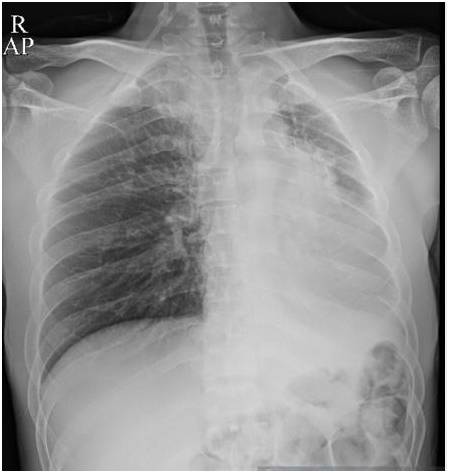

胸部前后位示弥漫不均匀的异常密度影,左肺体积缩小,左肺门区肿块样影与心膈角呈钝角。未增强纵隔窗CT示左肺肺不张,左主支气管完全受阻。增强CT示左主支气管及其段支气管内非强化的肿块。最小密度投影示左肺叶远端支气管重度狭窄,左主支气管及以下层面受阻。